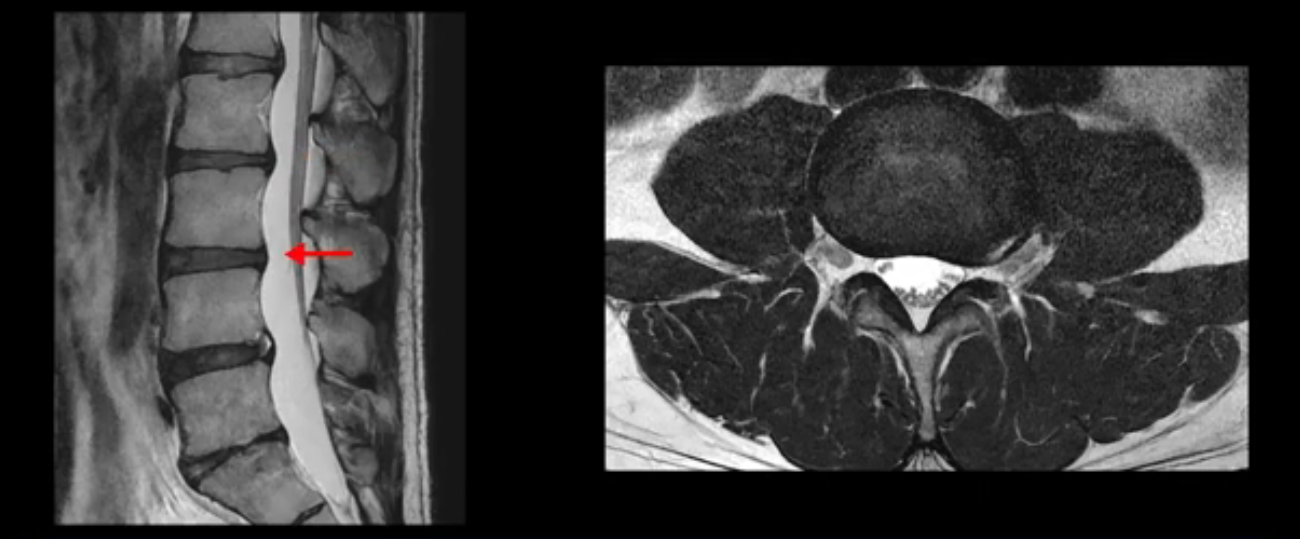

5번 1번 역시 가운데로 디스크 조금 밀려 나와있지만 신경 공간 넓이는 아주 넓어서 신경 눌림 있을 거라고 예상이 안됩니다.

추간공도 보시다시피 왼쪽, 오른쪽 전부 다 매우 넓어서 신경이 눌릴만한 부분이 전혀 보이지 않습니다.